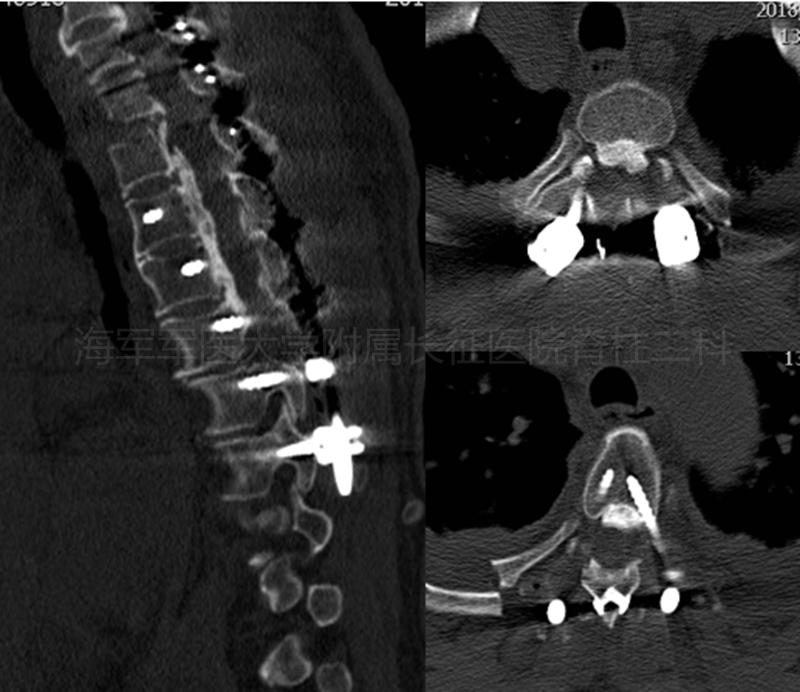

术前CT及平片

术前MRI

术后平片

术后CT

术后MRI